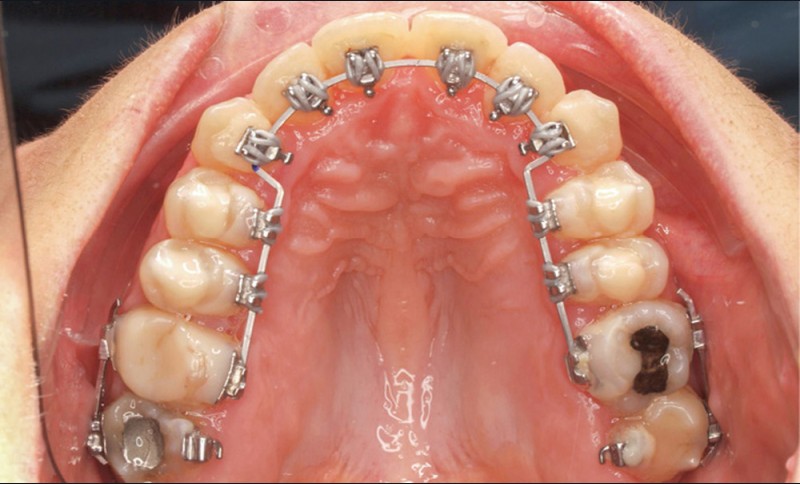

- Deuxième rendez-vous (fig. 2b) : les dents restantes sont collées et le même arc NiTi .014 est maintenu. Les cales rétro-incisives sont déposées et l’arcade mandibulaire est collée, un arc NiTi 0.014 posé.